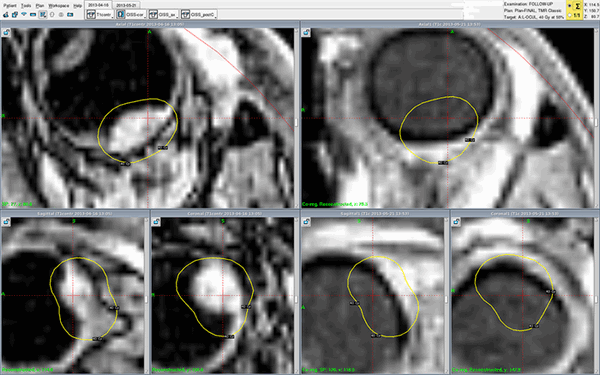

Риск нутритивной недостаточности по критериям MUST, опросникам NRS-2002 и ESMO был оценен как высокий. Учитывая соматическое состояние пациента, локализацию и объем опухолевого поражения, план биолучевого лечения по радикальной программе, в том числе объем облучения 520 см 3 , риск развития выраженных побочных эффектов лечения (мукозита, дерматита) также был оценен как высокий (рис. 2). Рис. 2. Дозное распределение при лучевом терапевтическом воздействии на локорегионарную область ротоглотки, включая заглоточные лимфатические узлы и лимфоколлекторы шеи Ib—IV групп с обеих сторон. PTV — планируемый объем облучения мишени; CTV — клинический объем мишени; GTV — макроскопический объем опухоли.

Реальный клинический случай - лечение меланомы хориоидеи Гамма-ножом Gamma-Knife Perfexion в Онкологической клинике МИБС. Снимки МРТ с контрастом (слева - до, справа - после лечения). Меланома хориоидеи на правом снимке, сделанном во время контрольного обследования всего через один месяц (!), не визуализируется - желтые контуры изначального расположения опухоли нанесены для сравнения. Опухоль исчезла. Без операции, с сохранением глазного яблока.